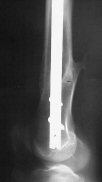

A new toy is more interesting and fashionable. And anyway it is not panacea, i have already seen presentations with LISS failures like the attached one presented by D.Seligson. And people also demonstrated incisions say that the method is not so LESS invasive as it supposed to be.